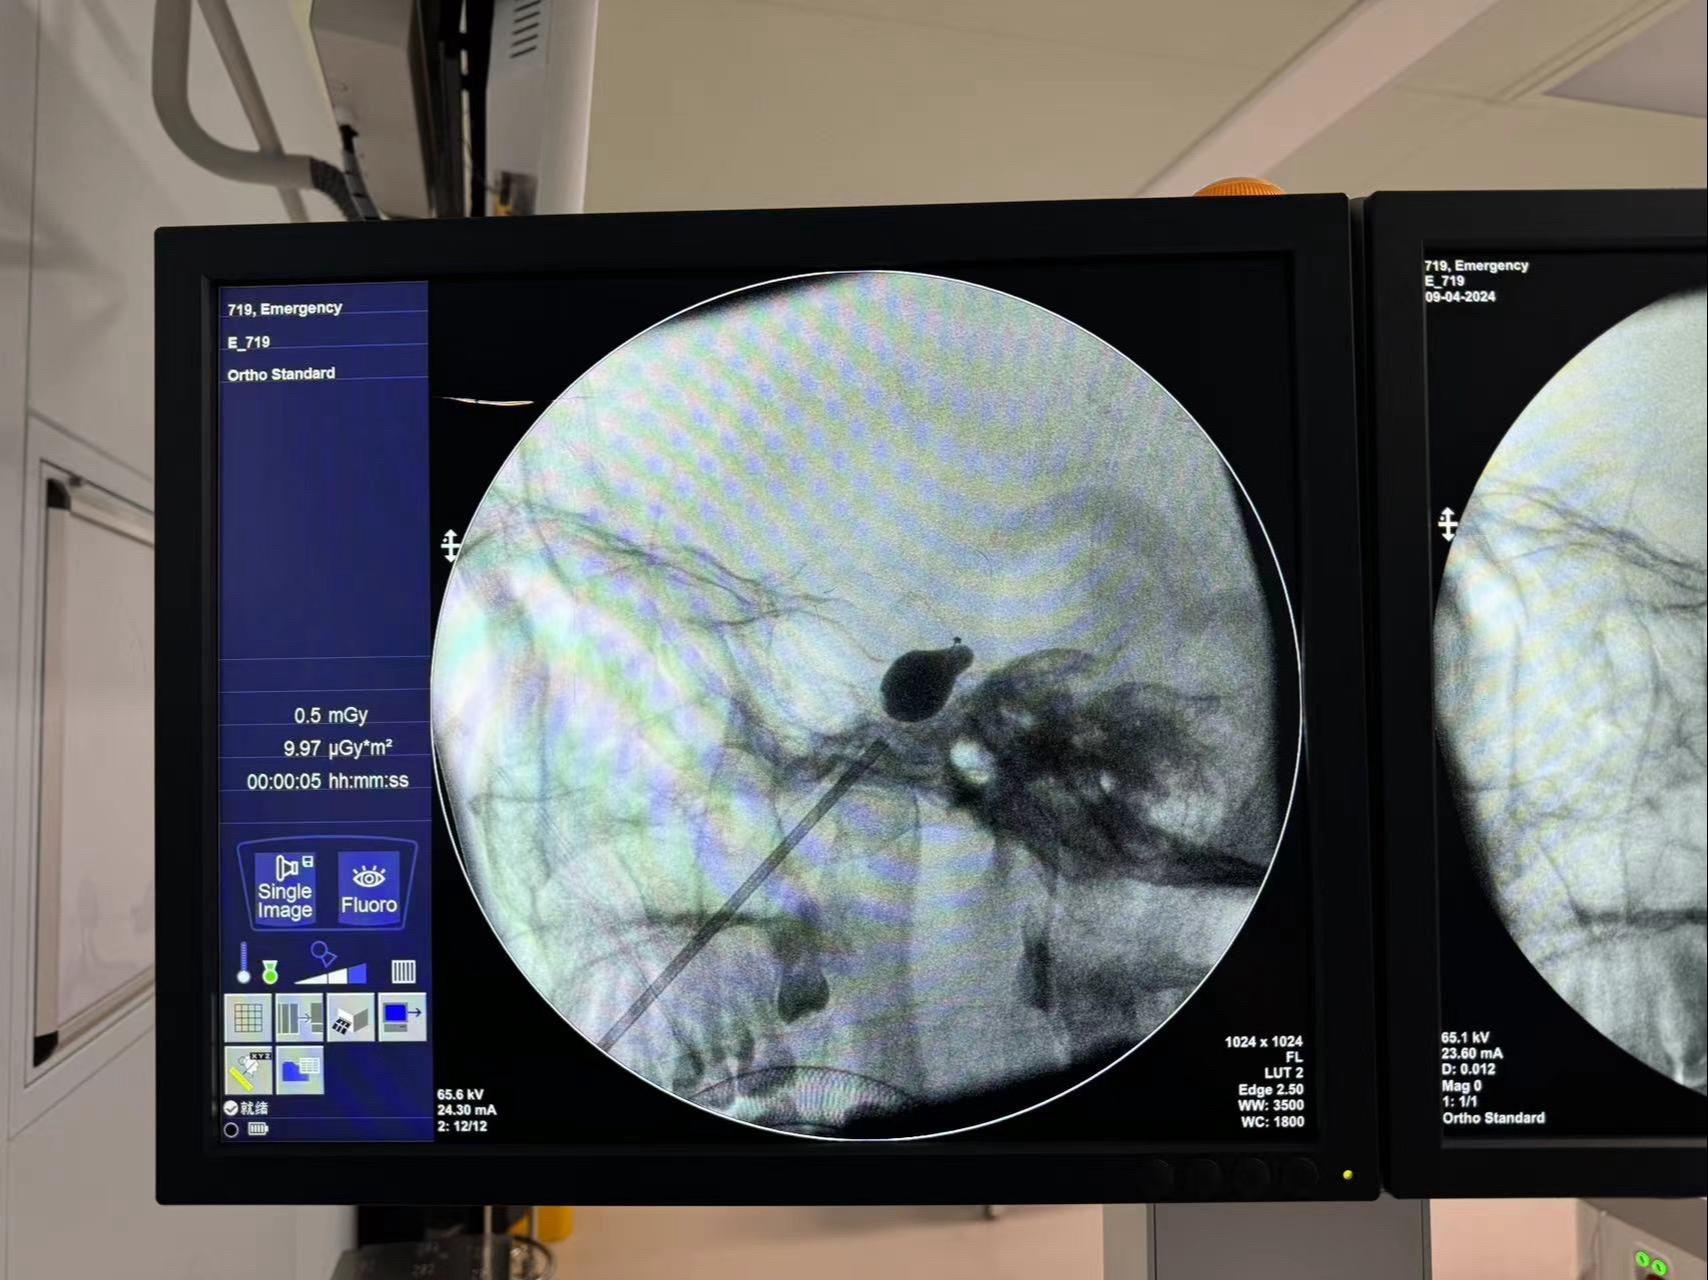

疼痛难忍。碰上这么一条“大蛇”(白色-椎基底动脉延长扩张)导致三叉神经痛,疼痛难忍,开颅风险较高,今日球囊手术顺利解决疼痛!